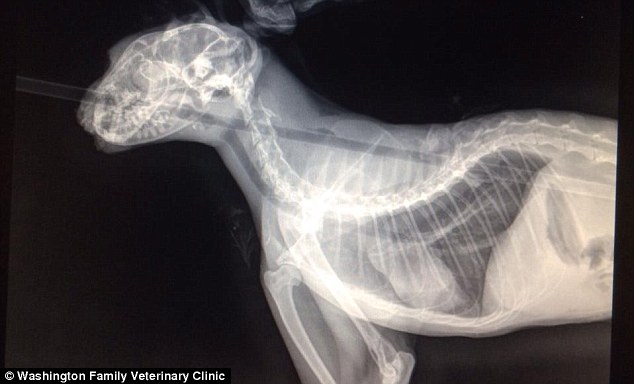

Этого кота исперили с лука, вывод простой - кто попадает в 6,5-7 см круг (обвод кошачьей морды по основание ушных раковин), играючи превратит в ежика особо умного варезовца.

Я уже боюсь комментить, а то опять скажут что я типа слишком умный, как бы это не звучало, но я и из лука стреляю. При стрельбе из лука есть один нюанс - расстояние. Не думаю что это выстрел со ста метров "белке в глаз". Скорее всего с пары-тройки метров, в неподвижную цель, ведь вряд ли кот атаковал стрелка аки тигр, верно?